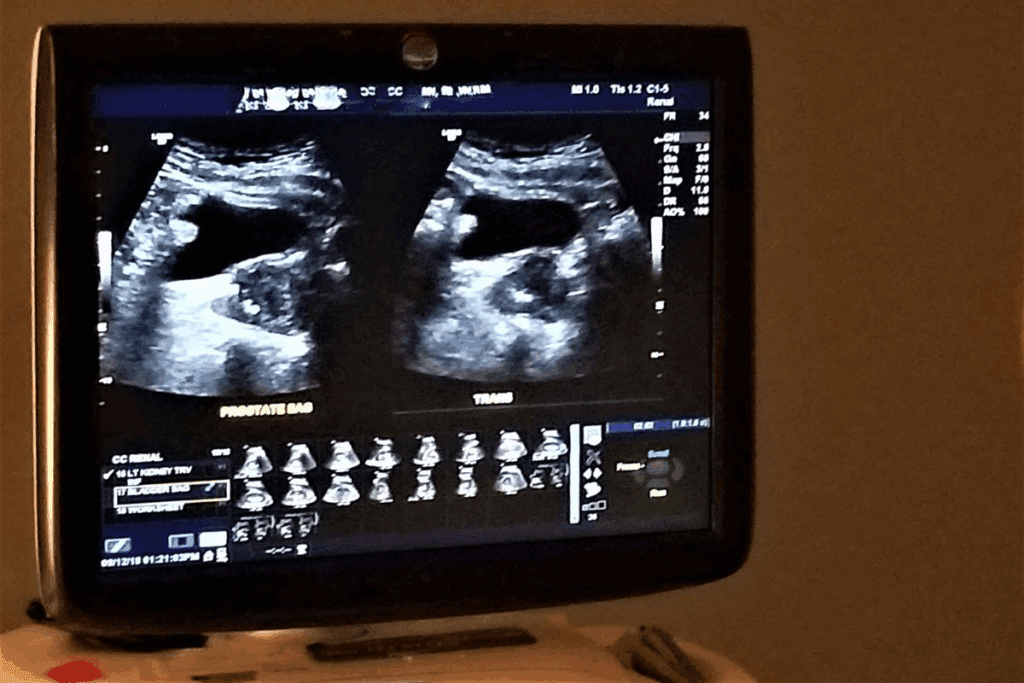

Diagnosing kidney disease needs blood and urine tests. The serum creatinine test checks for creatinine, a waste product. The estimated Glomerular Filtration Rate (eGFR) test shows kidney function based on creatinine, age, and sex.

Urine tests, like urinalysis, look for protein or blood in the urine. The urine albumin-to-creatinine ratio test finds albumin, showing kidney damage.